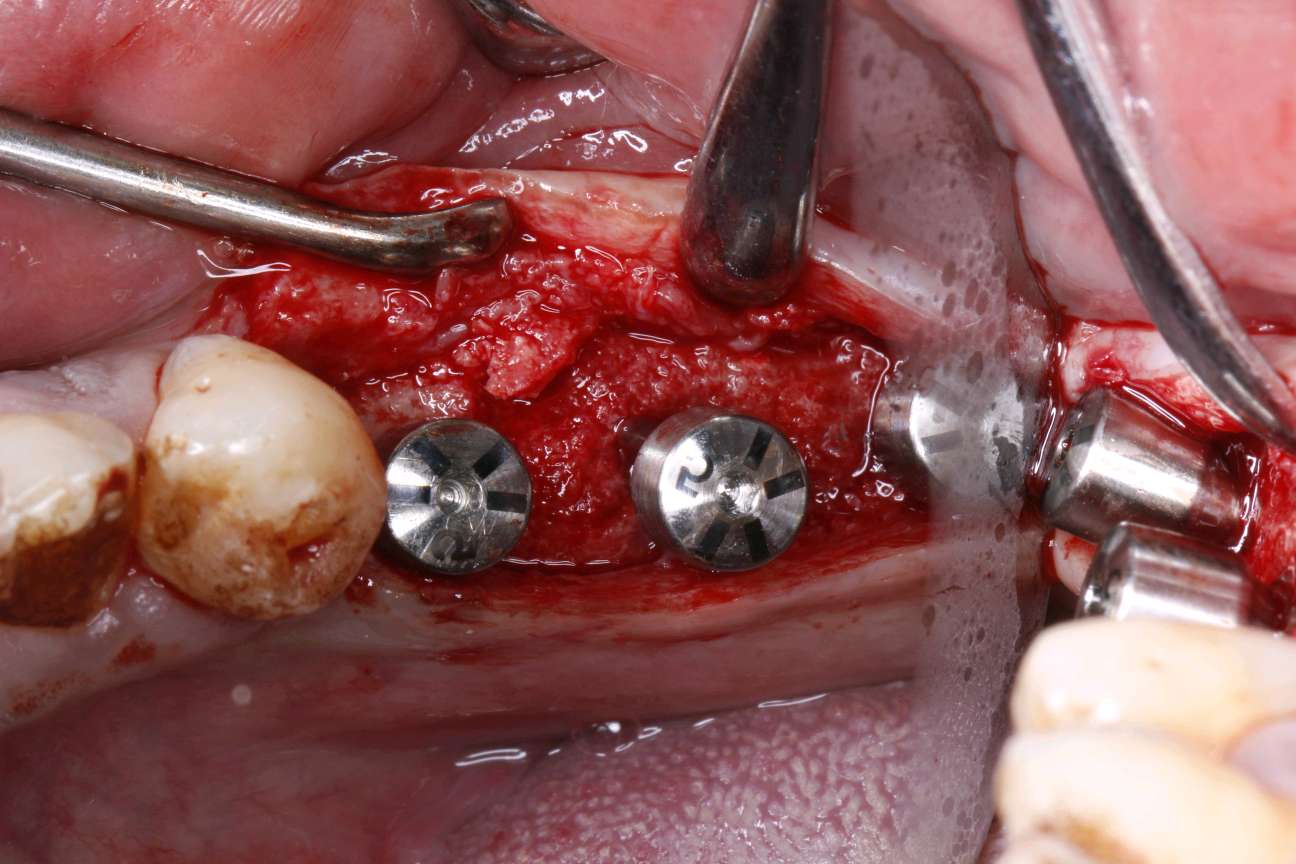

患者自愿选择安卓健种植体。牙槽嵴吸收较多,高度和宽度不足。拔出后植入骨粉骨膜。待骨条件良好后。35植入种植体4.0*10mm;36植入种植体4.6*10mm;37植入种植体4.6*8mm。待骨结合良好后。二期三期如期进行。余近日戴牙。

术中